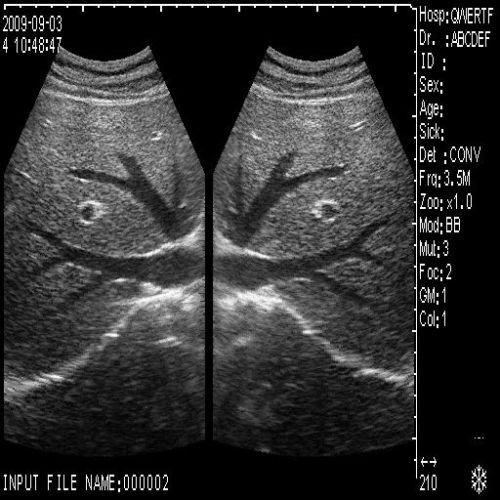

image: +3D High clear

Probe Function: 3.5MHZ convex, abdominal organs

The hospital ultrasound scanner is essential for providing high-quality imaging and diagnostics. It includes both convex and transvaginal probes, allowing for versatility in medical examinations. This equipment is designed to meet the rigorous demands of healthcare professionals, ensuring accurate results. Moreover, the 3D imaging feature helps in better visualization and assessment of patient conditions, which is critical in clinical decision-making.

This ultrasound scanner's dual probe system means that healthcare providers can easily switch between imaging modes. The convex probe is excellent for abdominal and fetal imaging, while the transvaginal probe allows for detailed pelvic examinations. Because of this flexibility, medical professionals can perform a wide variety of procedures without needing multiple machines. Therefore, hospitals can optimize their workflow and save valuable time.